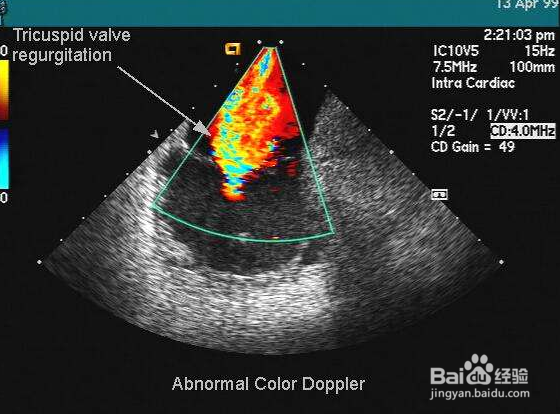

1、婴儿心脏彩超需要镇静,不能动来动去,需要深度睡眠。

我们一脸懵。是谁规定刚出生4个小时的婴儿必须做心脏彩超呢,回想当时小孩做心脏彩超时动静跟大,使劲哭的,跟疑问1矛盾。

2、先说镇静的问题,我们也不懂,我期初理解镇静就是麻醉,不管镇静麻醉,对婴儿神经、记忆,发育有影响吗?我们不清楚,但医生说没得影响的,安全的,我们是申请了专利的。我还是有点担忧,刚好做检查之前,小孩睡觉了,我抱进检查室去试一试,医生碰了两下,小孩还是睡着的,但他要动手,医生要的效果是,一点都不能动,心脏彩超不比其它类型的彩超,除非婴儿能听懂人话,不乱动就不用镇静了。我还是没有坚持住自己的立场,看来镇静是必须要做的了。检查完之后,庆幸小孩心脏是正常的。